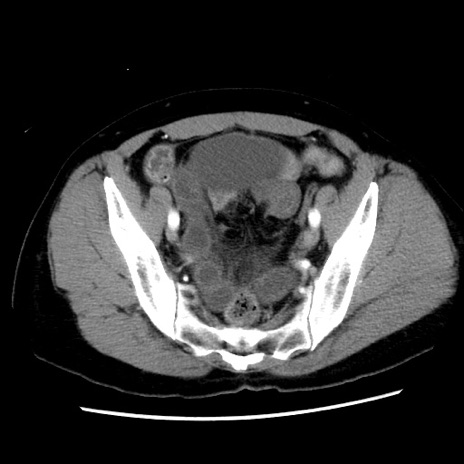

症例10(横断像)

【症例】 50歳代女性

【主訴】 腹痛

【現病歴】前日生レバーを食べた。今朝に排便あり。 昼前に突然発症の腹痛を生じ、当院救急外来を受診した。

【既往歴】 子宮筋腫にてで子宮全摘後

【身体所見】 意識清明、腹部:平坦、軟、下腹部やや左を中心に圧痛・反跳痛あり、筋性防御あり

【データ】WBC 7800、CRP 0.07